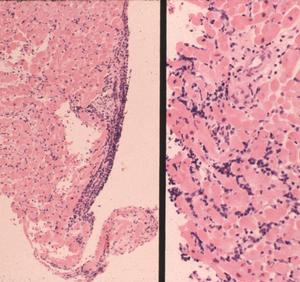

Patients in Europe have been seen with a lesion of skin referred to as Borrelia lymphocytoma or lymphadenosis benigna cutis, usually involving the ear lobe, lateral neck skin, or areola of the nipple. The histology is instantly recognizable by a marked dermal infiltrate of lymphocytes and other mononuclear inflammatory cells totally, or nearly totally replacing the dermis, with well-formed germinal centers (Fig. 3), as seen in lymph nodes or tonsillar lymphoid tissue, hence the term lymphadenosis. This is a remarkable lesion clinically and pathologically and is not always caused by Borrelia infection. When it is, however, the clinician should look for the spirochetes, which can be seen by silver stains. Other examples of early disseminated infection, which may be seen days to weeks following tick bite, include meningitis, radiculoneuritis, encephalopathy and Bell's palsy.

Another pattern seen in Lyme arthritis/synovitis is hypertrophic villous synovitis, a non-specific histologic lesion seen in other oligoarthritides, including undifferentiated arthritis. Here, the synovial surface is folded into fronds, yielding a villous appearance. Synovial surface cells are either of normal thickness or can thicken to 5-6 cells. The stroma of the villi demonstrate vascular proliferation (angiogenesis) to a degree that simulates a capillary hemangioma. Plasma cells are found in abundance in Lyme synovitis and are associated with large numbers of Giemsa stain-positive tissue mast cells.

Late disseminated infection of the skin is called acrodermatitis chronica atrophicans and occurs mainly in Europe. Histopathology in these cases is characterized by transdermal, comparatively dense and diffuse mononuclear inflammatory cells, including plasma cells, in association with dilated lymphatics (Fig. 6). The degree of these findings varies from case to case, but dermal inflammation is significantly greater than that of erythema migrans. Spirochetes can be demonstrated in many of these pathologic lesions except recurrent synovitis, which may be a molecular cross-reactive phenomenon. Spirochetes are always difficult to demonstrate in patients who have had prior or concurrent antibiotic therapy.